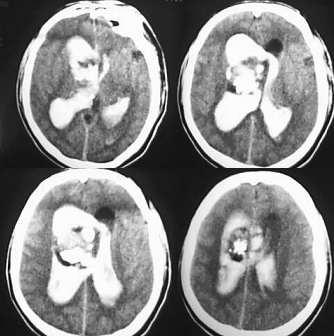

男39岁,今天早上1点多发病,来医院时病人已经昏迷.ct示脑室内出血在侧脑室顶部示有片状钙化

侧脑室扩大,脑室内大量出血,脑室内肿块阴影并钙化,脉络膜乳头状瘤继发出血可能。

钙化周围好象有脂肪密度影。

考虑:畸胎瘤破裂出血可能大。

脑室内出血铸型,脑室内可见较清楚的占位,脉络膜乳头状瘤、畸胎瘤、室管膜瘤都可以破裂后出血。

右侧侧脑室室间孔区肿块,内有大片钙化,双侧侧脑室出血、脑室铸形,考虑中枢神经细胞瘤合并出血。

鉴别:1、血管畸形,多位于侧脑室后部或三角区;

2、脉络膜丛乳头状瘤、室管膜瘤多小于5岁发病,常位于三角区;

3、室管膜下巨细胞星形细胞瘤钙化很少见。